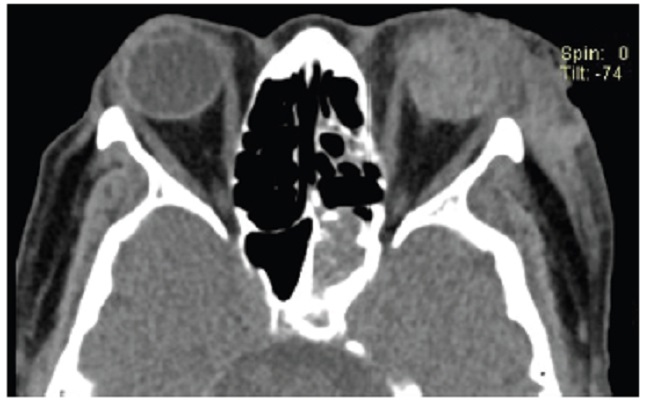

Las calcificaciones oculares y el material médico se pueden confundir con cuerpos extraños u otras lesiones orbitarias1. Las localizaciones típicas de las calcificaciones permiten diferenciarlas de cuerpos extraños hiperdensos. Las más frecuentes son las calcificaciones trocleares, las placas esclerales, las drusas del nervio óptico y la ptisis bulbi. Las primeras tienen localización superomedial dentro de la órbita (Fig. 13), en la tróclea del músculo oblicuo superior, aunque se pueden observar en todas las edades, hay mayor prevalencia de calcificaciones trocleares en pacientes con enfermedades autoinmunes y niveles elevados de fosfatasas alcalinas. Las placas esclerales se localizan en los sitios de inserción de los músculos rectos medial y lateral (Fig. 14) y son más comunes en los pacientes ancianos. Las calcificaciones que ocurren cerca del disco óptico se conocen como drusas del nervio óptico (Fig. 15), las cuales se asocian a degeneración macular y pueden ser causa de pseudopapiledema benigno. La ptisis bulbi es una atrofia y calcificación del globo ocular como secuela de enfermedades infecciosas, inflamatorias o traumáticas previas (Fig. 16) (1,11. Los imitadores de lesiones abiertas del globo ocular incluyen las deformidades como coloboma, estafiloma y el globo ocular elongado por glaucoma o miopía (Fig. 17). Las masas orbitarias y los hematomas también pueden alterar el contorno del globo ocular y asociarse a calcificaciones o relacionarse con desprendimiento de retina (Fig. 18) (1,6,8,11.